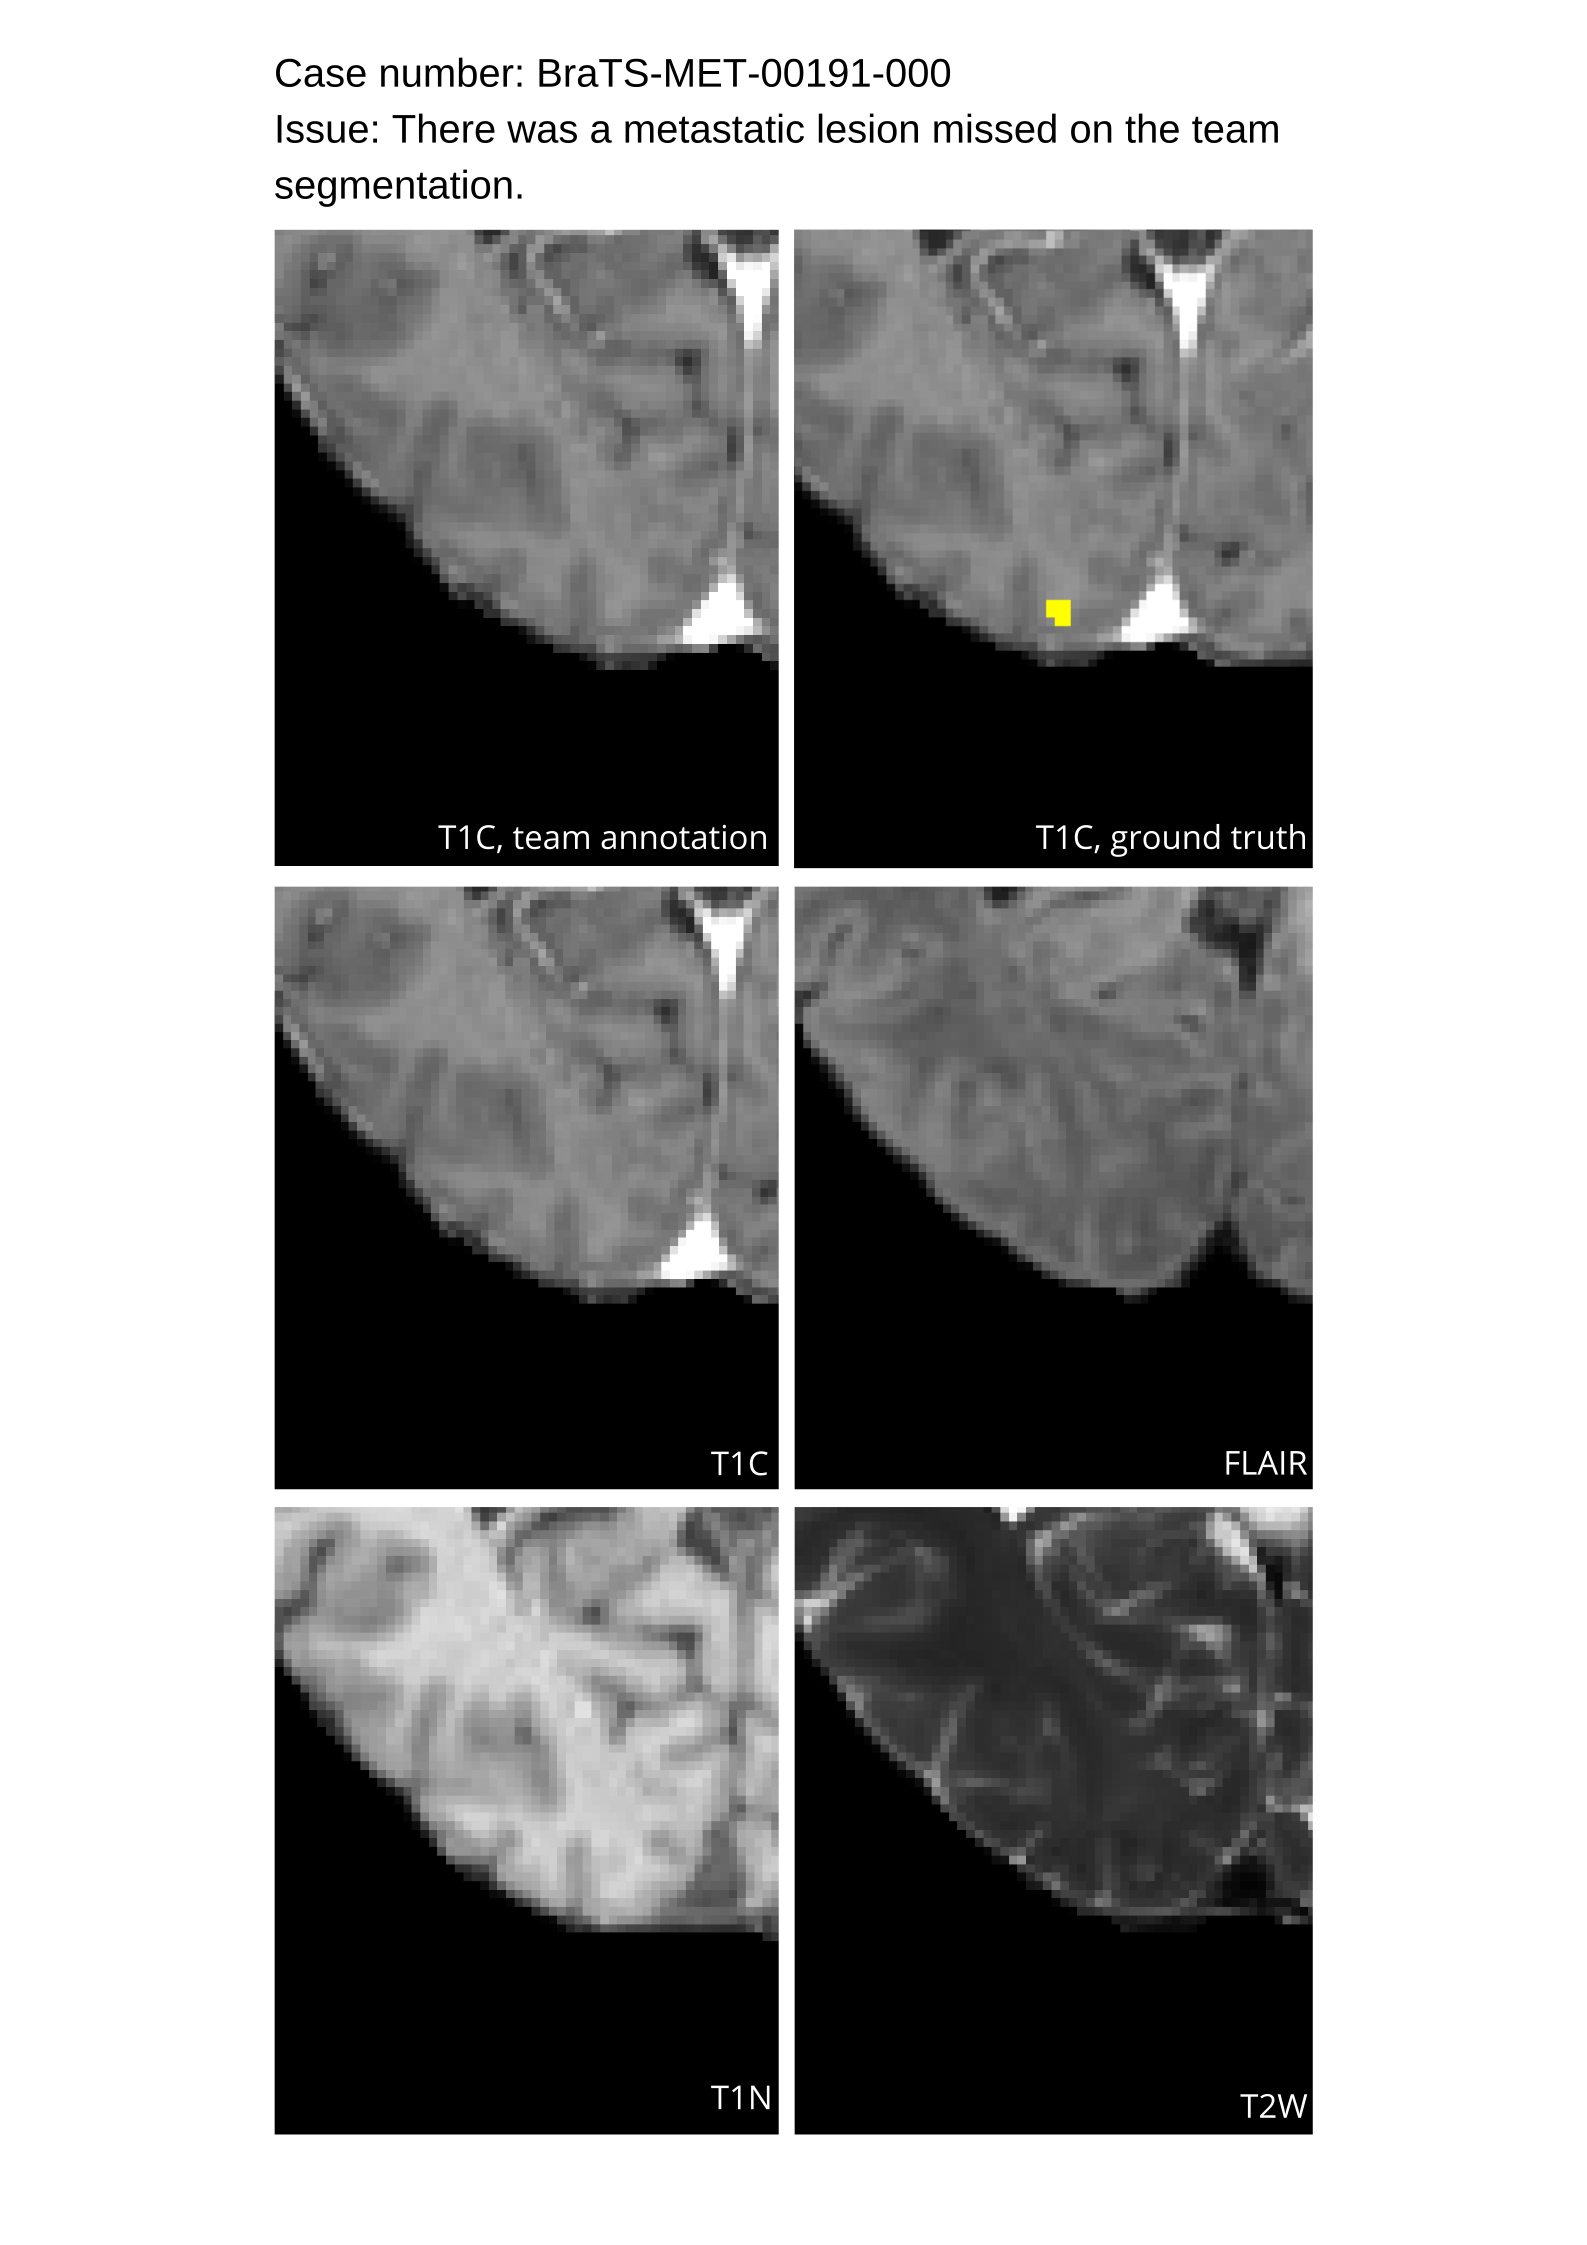

Table 4 provides the relative ranking for each team. Team NVAUTO ranked first in the challenge, with an average rank across subjects of 7.9 and a PatientWise mean of 0.38. Team SY placed second with a PatientWise mean of 0.41 across all patients. The supplementary material depicts the pitfall cases with figures illustrating the false positives or missed lesions.